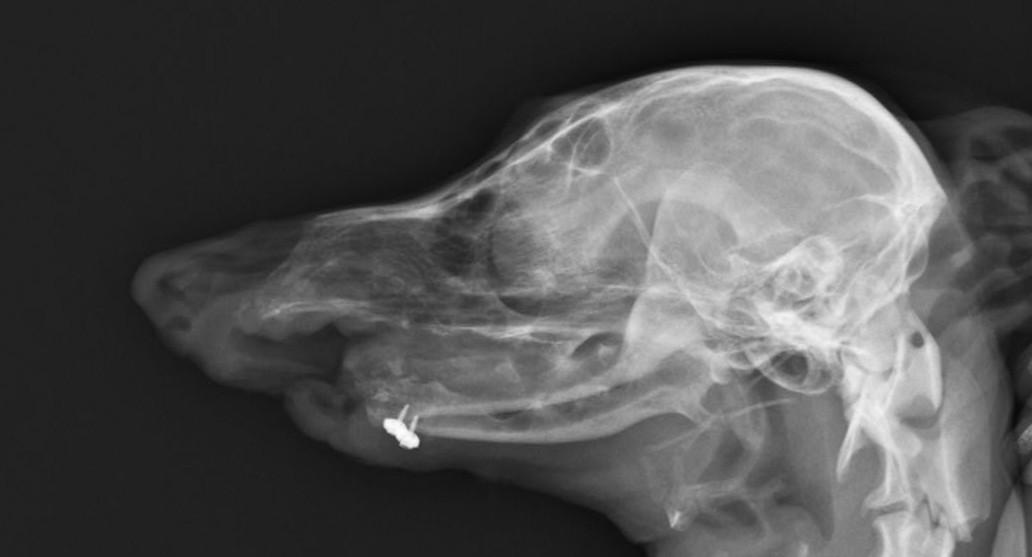

ワンちゃんが乳腺にできた複数のシコリを気にされて来院されました。bilateral mastectomyで対応しました。摘出後の病理組織検査の結果は、「R3-4間腫瘤:乳腺癌(複合型)」でそれ以外は「良性乳腺混合腫瘍」でした。無事元気に退院し、その後再発もなく経過は良好です。よかったね。